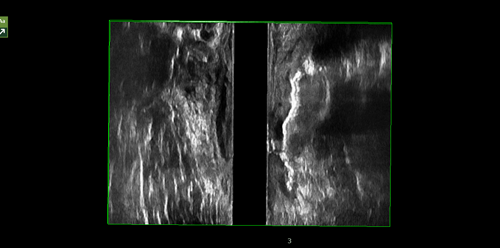

(2)直肠阴道瘘诊断

直肠阴道瘘是连接直肠前壁和阴道后壁之间的异常病理性通道,病因多样,表现形式有差异。由于病变发生的解剖间隙层次复杂,缺少超声对比窗口,瘘道不易识别,过氧化氢造影超声诊断技术可以明确瘘道路径及在肛管直肠或阴道侧的开口。